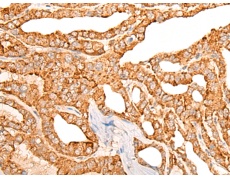

IHC positive control: |

Human thyroid cancer |